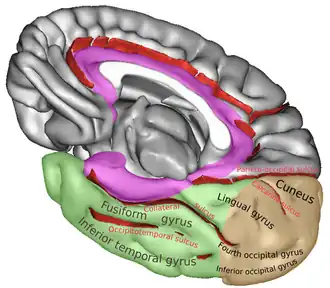

Infero-medial surface of right cerebral hemisphere. The color brown represents occipital lobe.

Infero-medial surface of right cerebral hemisphere. The color brown represents occipital lobe. -